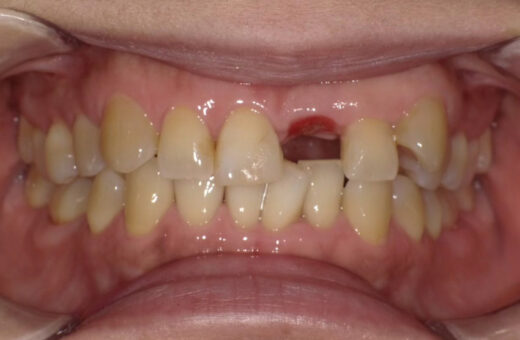

インプラント治療 50代(女性)

治療前

主訴

左上前歯が硬いものを噛んでしまって動いている

症例詳細